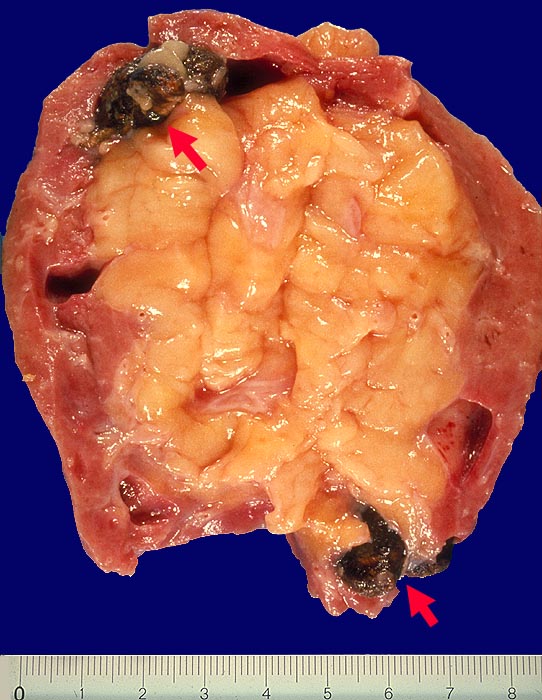

Chronische Pyelonephritis bei Steinniere

In mehreren Kelchen findet man festgefahrene Konkremente. Herdförmig hochgradige Vernarbung des Nierenparenchyms. An anderer Stelle ist der Parenchymsaum besser erhalten. Vakatfettwucherung des subpelvinen Fettgewebes.

Nephrektomie auf der einen Seite vor 23 Jahren. Jetzt Nephrektomie auf der anderen Seite nach 16-monatiger Dialyse wegen akuter Pyelonephritis.